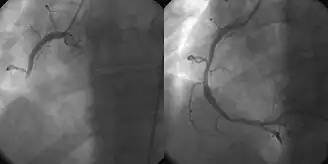

- Intervenção coronária percutânea (ICP/angioplastia coronária)

Animação Médica 3D ainda filmada de intervenção coronária percutânea - o uso da angioplastia para o tratamento da obstrução das artérias coronárias em decorrência de doença arterial coronariana. Um cateter balão vazio é introduzido na artéria obstruída e insuflado para aliviar o estreitamento; certos dispositivos, como stents coronários, podem ser implantados para manter o vaso sanguíneo aberto. Vários outros procedimentos também podem ser realizados ao mesmo tempo. Após um infarto, pode ser restrito ao vaso culpado (aquele cuja obstrução ou trombose é suspeita de causar o evento) ou revascularização completa; a revascularização completa é mais eficaz em termos de eventos cardíacos adversos maiores e mortalidade por todas as causas.[4]